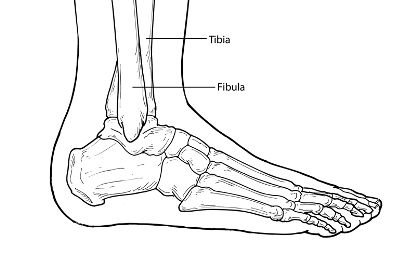

A fracture is a partial or complete break in a bone. Fractures in the ankle can range from the less serious avulsion injuries (small pieces of bone that have been pulled off) to severe shattering-type breaks of the tibia, fibula, or both.